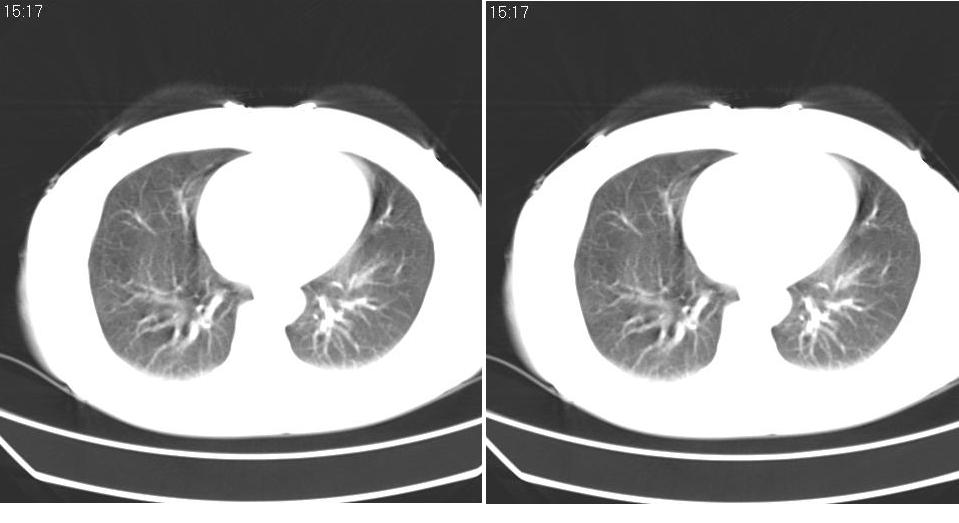

女 40岁,胸片体检发现右肺肿块,无任何症状。

下叶背段多发性小腺泡结节,考虑结核。

考虑右肺下叶背段继发性肺结核。